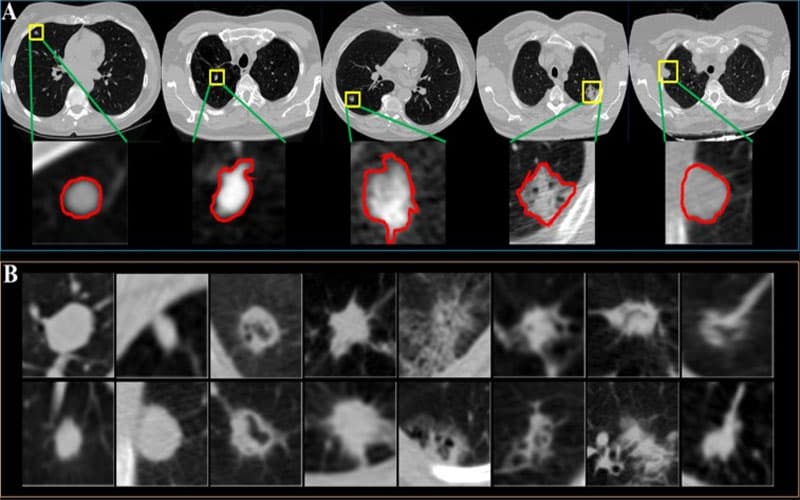

U phổi lành tính là sự tăng trưởng bất thường của các mô trong phổi nhưng không phải là ung thư. Khác với các khối u ác tính, các tế bào trong khối u lành tính không xâm lấn vào các mô xung quanh và không di căn (lan rộng) đến các bộ phận khác của cơ thể và thường có ranh giới rõ ràng trên phim chụp X-quang hoặc CT.